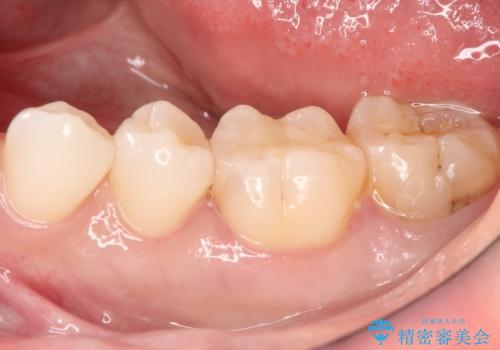

セラミックインレー 虫歯で欠けた歯の治療